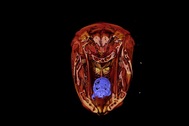

Hình ảnh nội soi rận mu trên kính hiển vi (Ảnh: Bệnh viện cung cấp).

Qua thăm khám, bệnh nhân được chỉ định xét nghiệm tìm ký sinh trùng trên cơ thể (nạo, soi da và lông nách dưới kính hiển vi). Kết quả xét nghiệm phát hiện nhiều trứng rận (rận mu) bám chắc trên lông, còn ấu trùng rận và rận trưởng thành bám chắc vào da vùng nách.